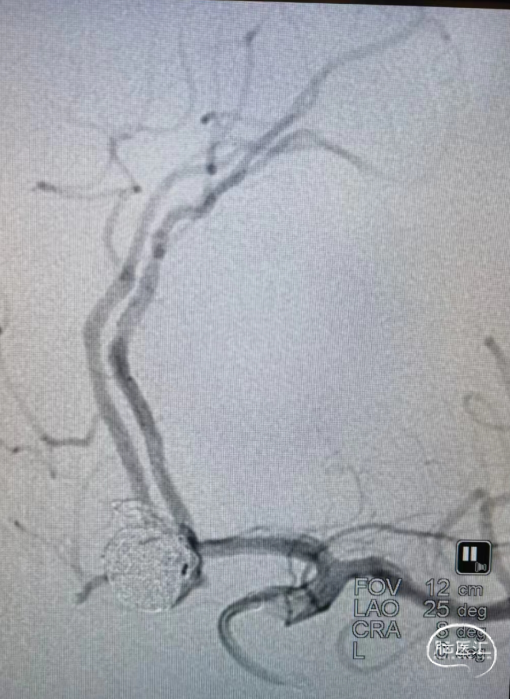

CTA:见前交通动脉瘤,大脑前动脉共干,动脉瘤16*10*9大小,双侧A2均由动脉瘤上发出,右侧A2开口呈180°回旋。

沿微导管(0.017" 微导管)填入第一个通桥凤®弹簧圈AEC-12-40-S,成篮,圈填塞一半后,沿0.021" 微导管半释放ENCR402300 (4.0*23mm)支架进行辅助栓塞。

沿微导管(0.017" 微导管)继续填塞第一个成篮圈:通桥凤®弹簧圈AEC-12-40-S,成功解脱;填塞第二个通桥凤®弹簧圈AEC-09-30-S,成功解脱后依次填塞弹簧圈。

填塞第七个通桥凤®弹簧圈AEC-04-12-S。

继续填塞第七个通桥凤®弹簧圈AEC-04-12-S,进行收尾,释放EP2支架。

术后造影:弹簧圈致密填塞。

栓塞后造影:动脉瘤致密填塞。